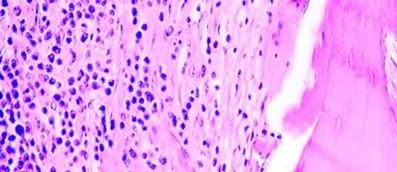

In non-metastatic high-grade osteosarcoma, the extent of tumor necrosis following neoadjuvant chemotherapy is the single most important prognostic indicator. A good response is defined as >90% necrosis (Huvos grade III or IV) and correlates highly with increased overall and disease-free survival.

The degree of tumor necrosis following neoadjuvant chemotherapy is the single most important prognostic factor for overall survival in patients with localized high-grade osteosarcoma. A 'good response' is defined as >90% tumor necrosis (Huvos grade III or IV) and is associated with significantly higher 5-year survival rates compared to poor responders (<90% necrosis). While tumor size and initial lab markers have prognostic value, histologic response is the most highly predictive metric.